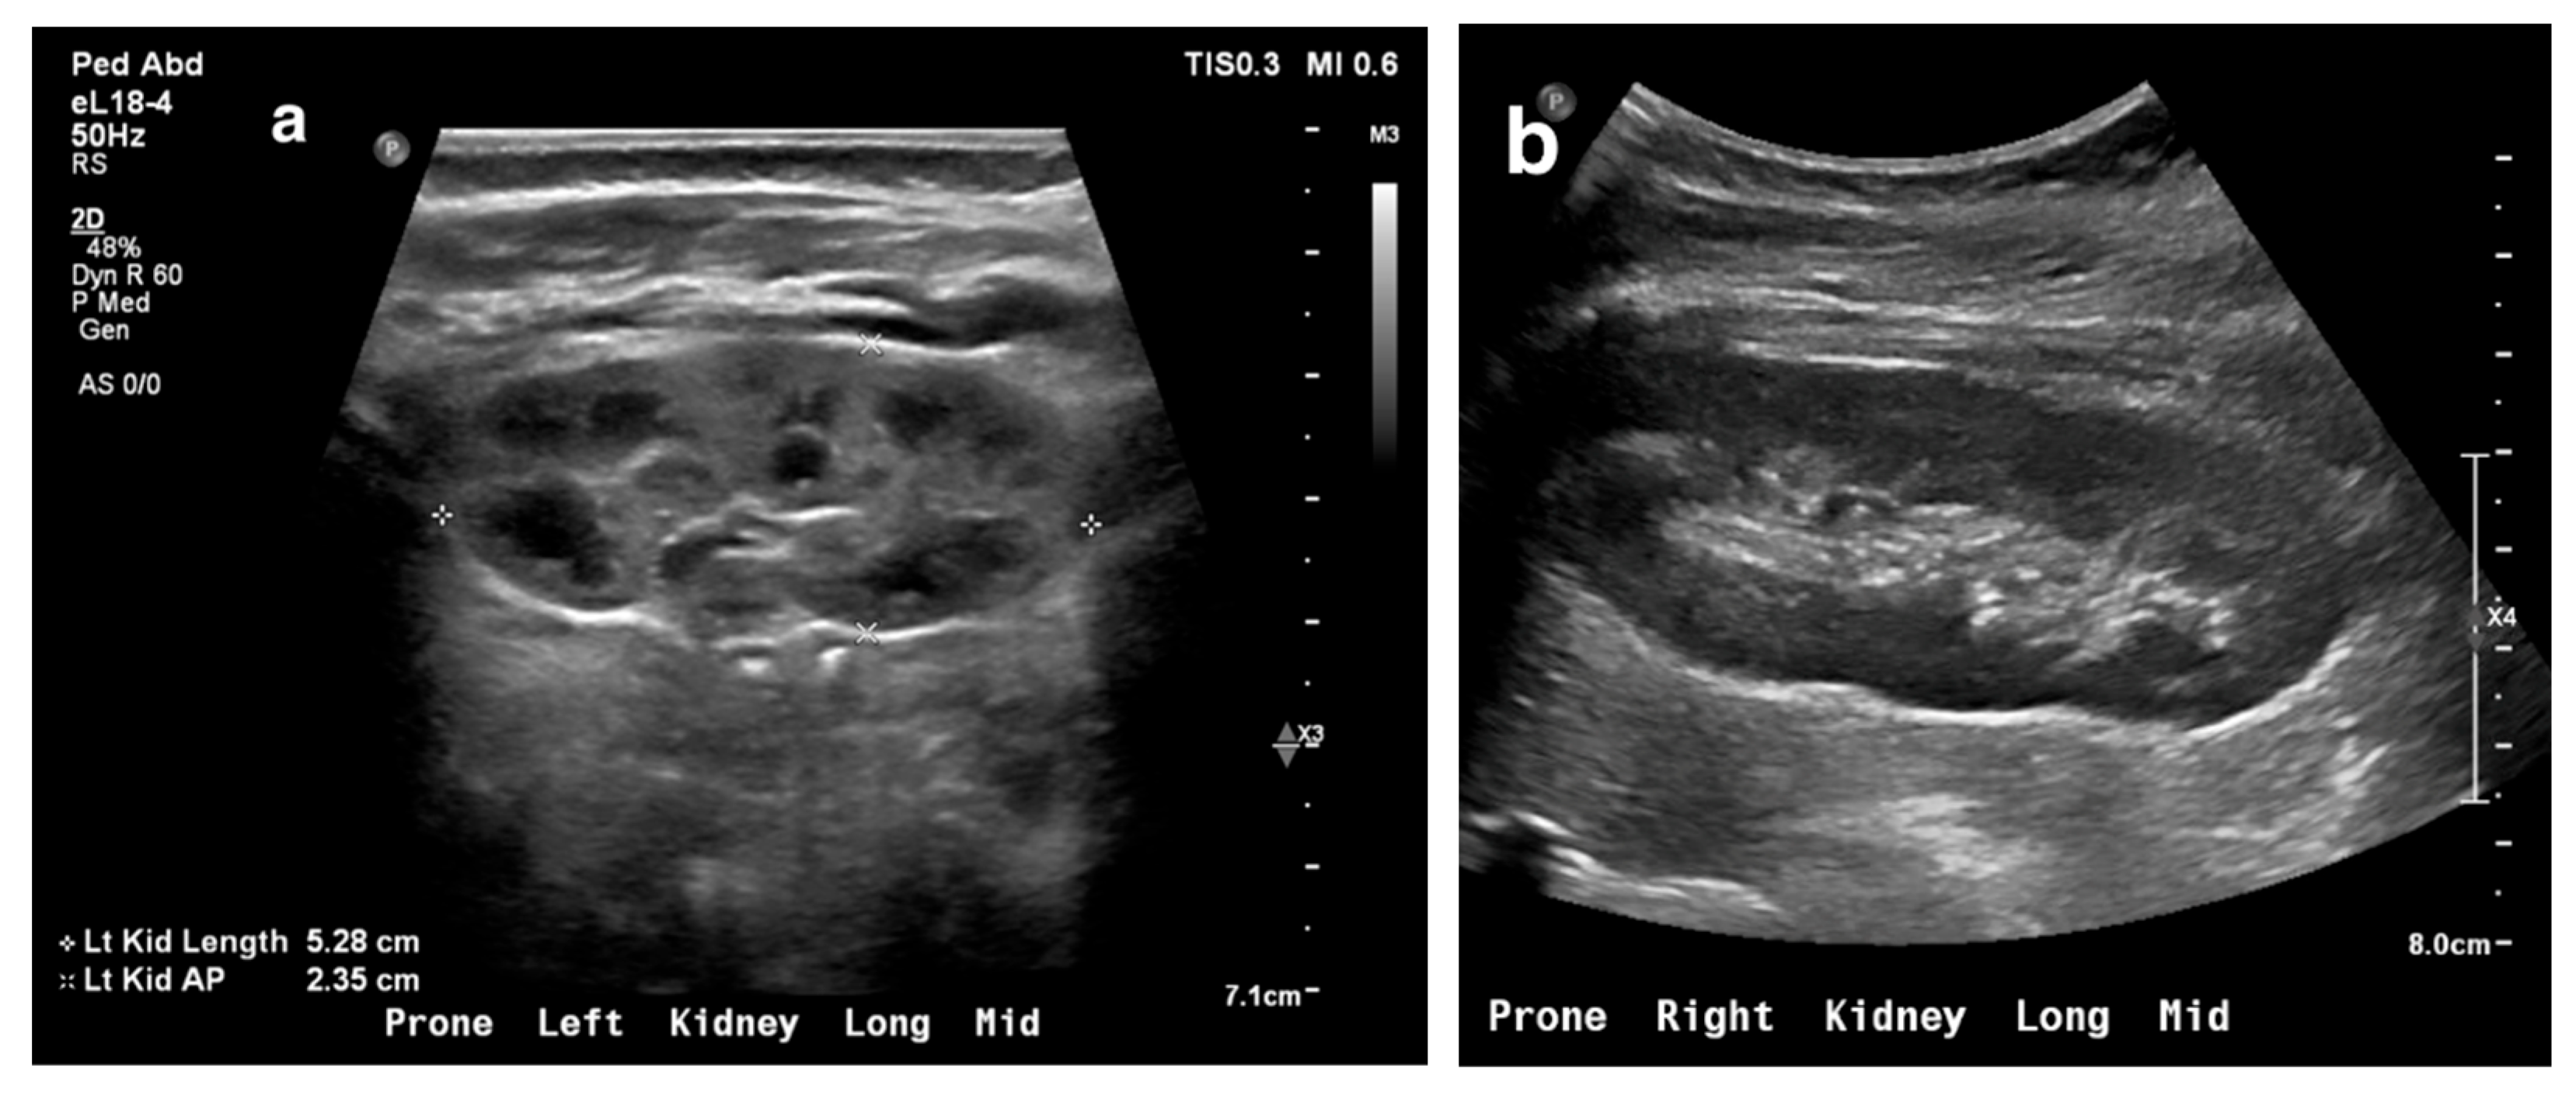

17. Cystic Kidney Disease

Autosomal recessive polycystic kidney disease (ARPKD) presents with a broad clinical spectrum, from severe perinatal forms to minimal renal disease with dominant hepatic fibrosis. Ultrasound (US) is the initial diagnostic tool, typically showing enlarged, echogenic kidneys with poor corticomedullary differentiation. Microcysts are not visible on US, but macrocysts may be seen in older children (Figure 18) [65,66,67].

Figure 18. (a) ARPKD in a 5-day-old male identified by enlarged, echogenic kidneys with poor corticomedullary differentiation, without visible renal cysts. (b) A 6-year-old female with ARPKD, presenting with significantly enlarged kidneys and macrocysts (highlighted by green arrows).